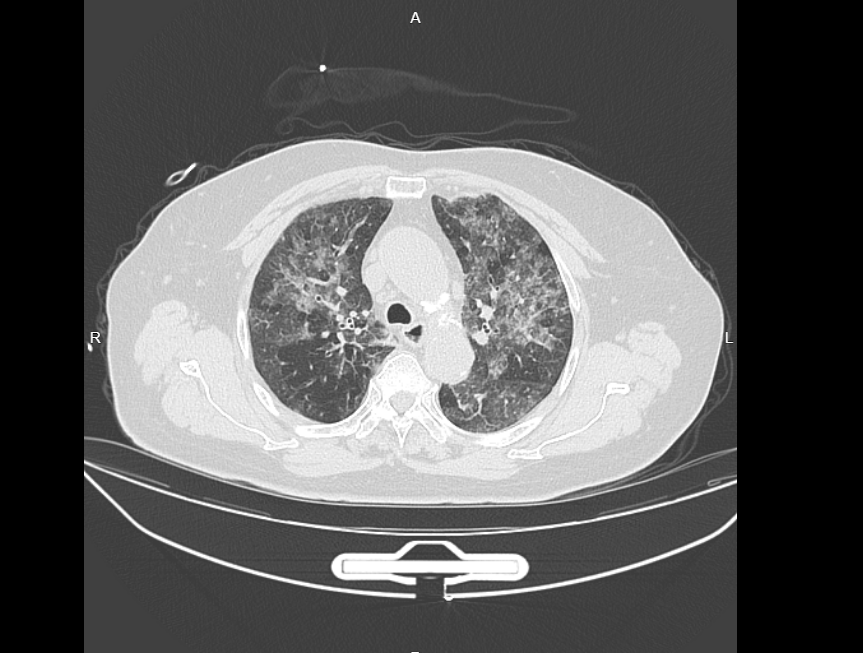

丁群力检查发现,张奶奶的肺部CT呈现弥漫性“白影”(俗称“白肺”),密密麻麻都是白斑,肺功能仅为正常值的60%,稍稍活动后就开始大口喘气,连日常行走都倍感吃力。由于抗生素药物治疗无效,而且症状表现与外源性过敏性肺泡炎相似,丁群力通过激素对症治疗,暂时缓解了张奶奶的症状,并叮嘱张奶奶:“您这段时间尽量留意一下,有没有长期接触烟雾、粉尘这类刺激性东西,好好排查一下可能导致吸入的源头,要是找到了一定要及时避开,不然病情可能会反复。”

CT显示肺部全是白色的炎症反应

令人没想到的是,4个月后,张奶奶再次来到了丁群力的门诊,她的病情突然复发,咳嗽、气急症状甚至比第一次更严重,复查CT显示肺部白影范围明显扩大,炎症指标也再度飙升。

经过规范治疗,在近期复查时,张奶奶肺部白影已明显变淡,肺功能也提升至接近正常值的80%,但肺部仍有斑驳的损伤痕迹,还需要长期调理恢复。